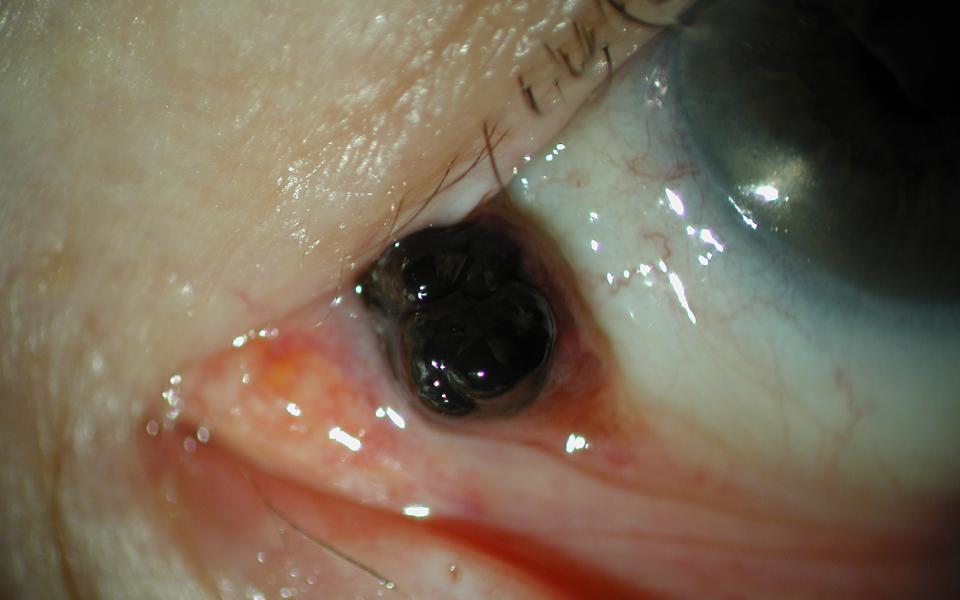

This is a 25 Asian male presenting with a melanocytoma of his caruncle. It had been present for many years but thought to be growing. He underwent excision with histology confirming the diagnosis.